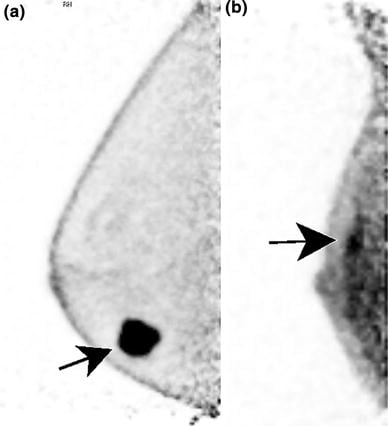

PET Scan for Mammography (3D) - Detect potential tumors or lesions using Positron Emission Tomography